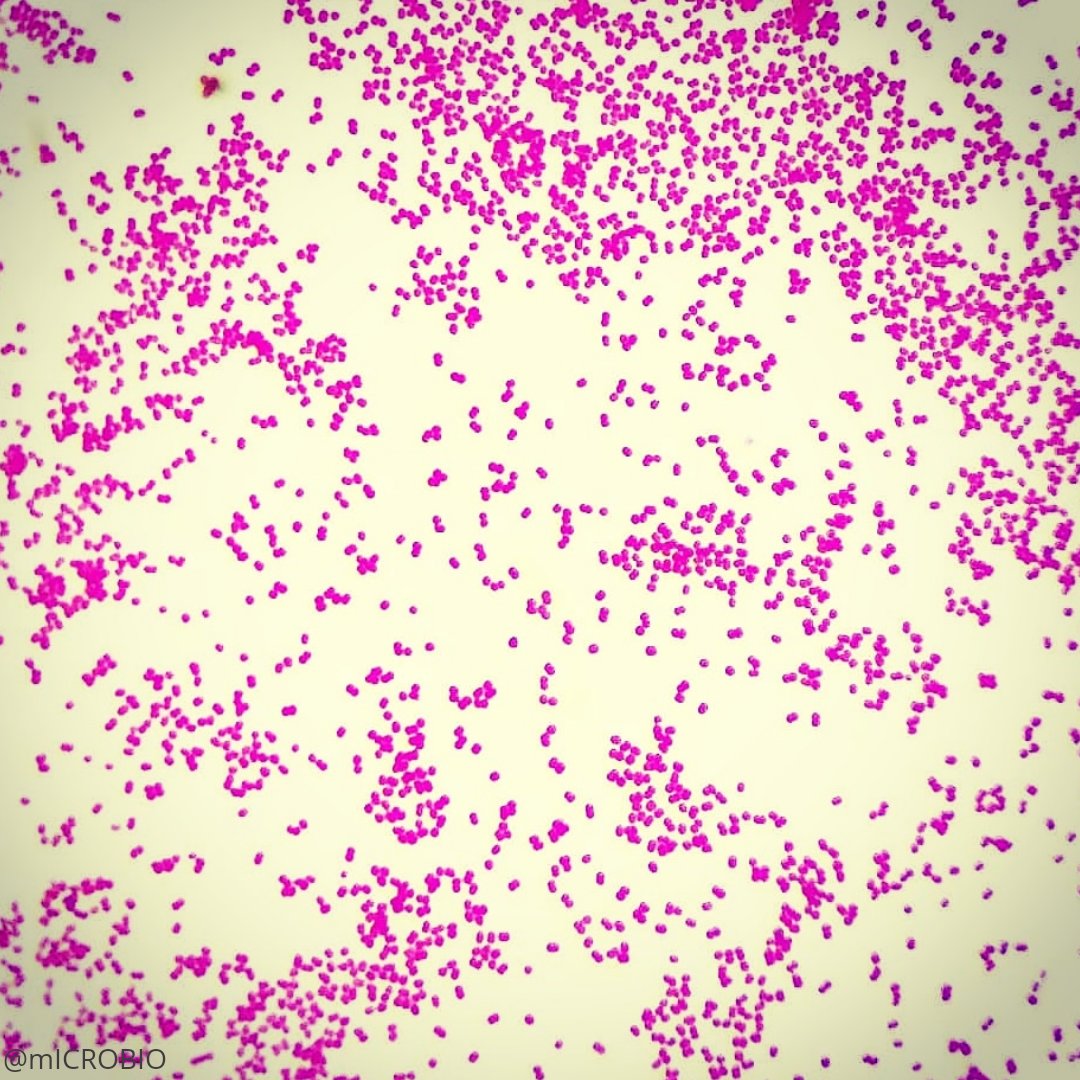

Esta enfermedad es producida por varias bacterias; de ellas, la más conocida es la Gardnerella vaginalis, también llamada Haemophilus vaginalis. Esta bacteria pertenece a la familia de los Bifodobacterium.

En caso de duda se puede efectuar un frotis, que consiste en tomar una muestra y analizarla al microscopio. También se puede realizar un cultivo. Existe adicionalmente una prueba sencilla: se agrega hidróxido de potasio a una muestra de la secreción; si la gardnerella está presente, despedirá un olor a pescado característico.